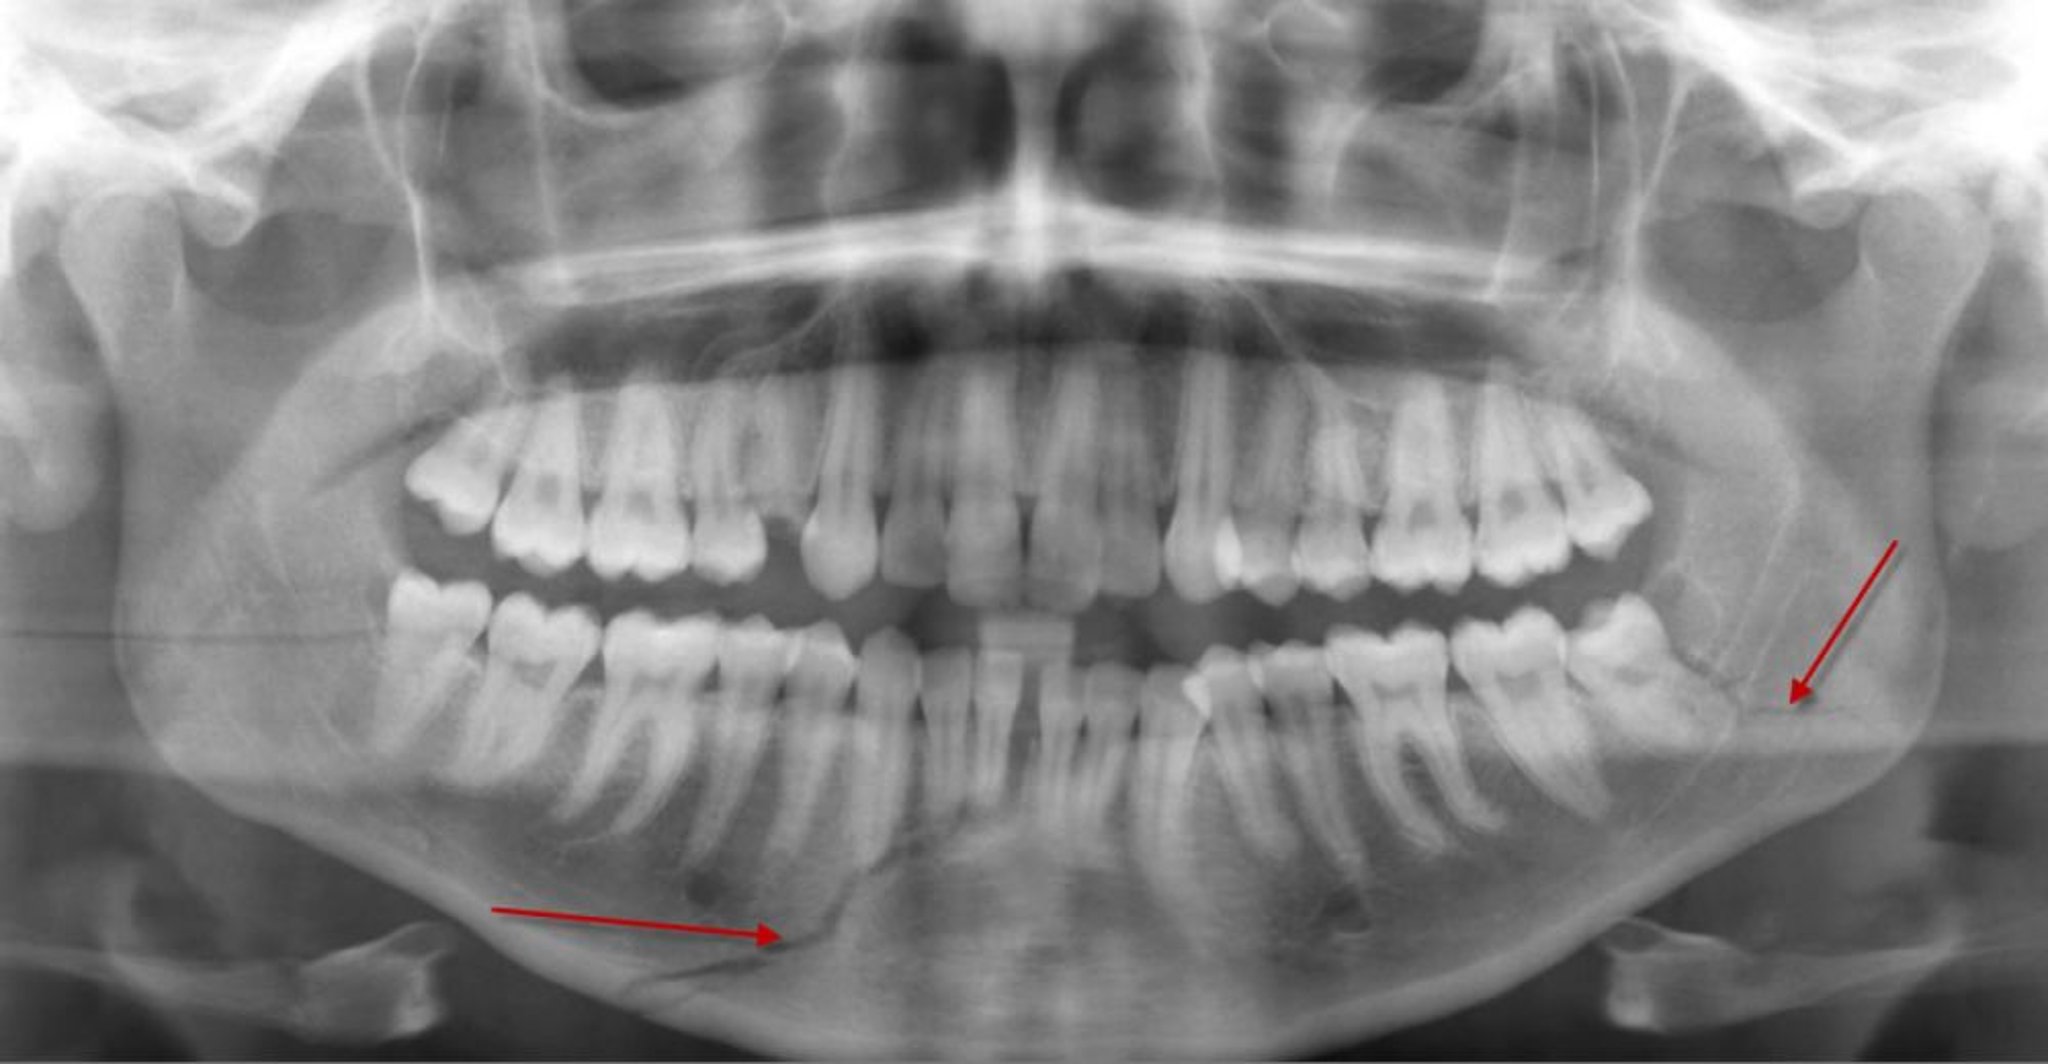

Fracture du corps mandibulaire

Cette radiographie panoramique montre une radiotransparence (flèche du bas) dans le corps de la mandibule, représentant une fracture, qui atteint les racines de certaines dents antérieures inférieures. Il existe également une fracture de l'angle mandibulaire gauche (flèche).